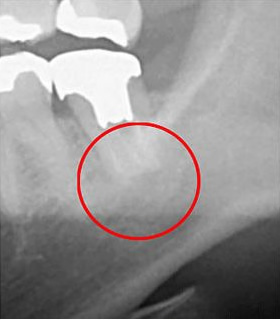

以下は、同じ歯をCTとレントゲンで撮影した画像の比較です。

• 画像

CT画像

レントゲン画像

左の写真では黒い影が見えますが、右の写真にはありません。実はこの黒い影が、歯の根の炎症です。

つまりレントゲン検査だけだと炎症を発見できず、見逃してしまう可能性があるということです。CTを使うことで、初期の炎症も見逃すことなく、適切な診断ができます